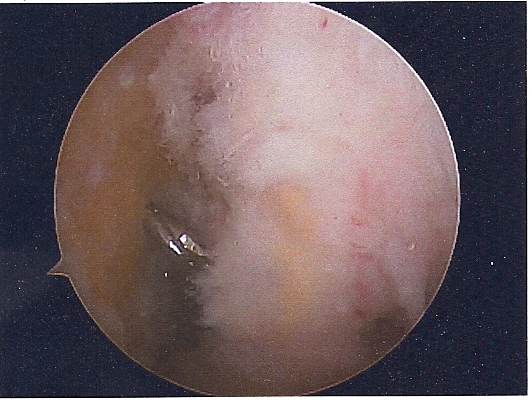

She had ACL replacement surgery on March 28th, using Bone-Patellar-Bone graft from her own patellar tendon. These are the images are scanned from pictures taken by the scope during the surgery. We were supposed to get a DVD of the procedure, but forgot to remind him on the day of the surgery. Oh well...

PF JOINT